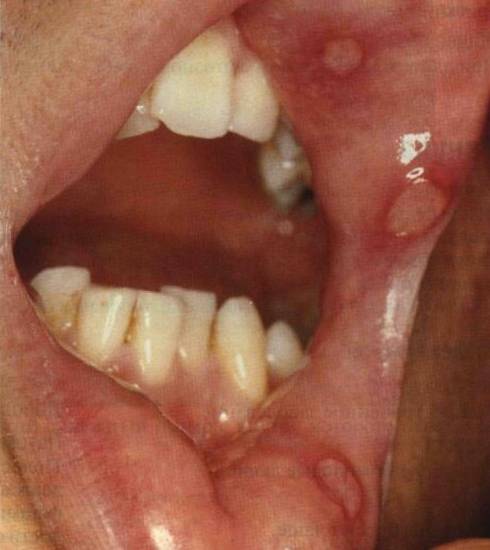

При заражении в результате нестандартных половых контактов очаги поражения могут находиться в области головы – во рту, на языке, в глотке и миндалинах, на губах, молочных железах, около анального отверстия или в других частях тела. В некоторых случаях местом локализации могут стать уретра у мужчин, а также стенки влагалища и шейка матки у женщин.

Сначала на коже возникает небольшой красноватый отек с приподнятыми и неровными краями. Язва имеет неправильную форму, ярко-красный цвет и выделяет значительное количество гноя. Одним из ярких признаков мягкого шанкра является увеличение местных лимфоузлов.

Название «венерическая язва» связано с тем, что она чаще всего образуется на половых органах. Появление шанкра сопровождается выраженными болевыми ощущениями.

Основным признаком формирования мягкого шанкра на ранних этапах является возникновение язвы – шанкароида, которая обладает следующими характеристиками:

- мягкое основание;

- наличие гноя на дне язвы;

- развитие воспалительного процесса;

- возможные кровотечения;

- острые болевые ощущения (у мужчин этот синдром менее выражен по сравнению с женщинами).